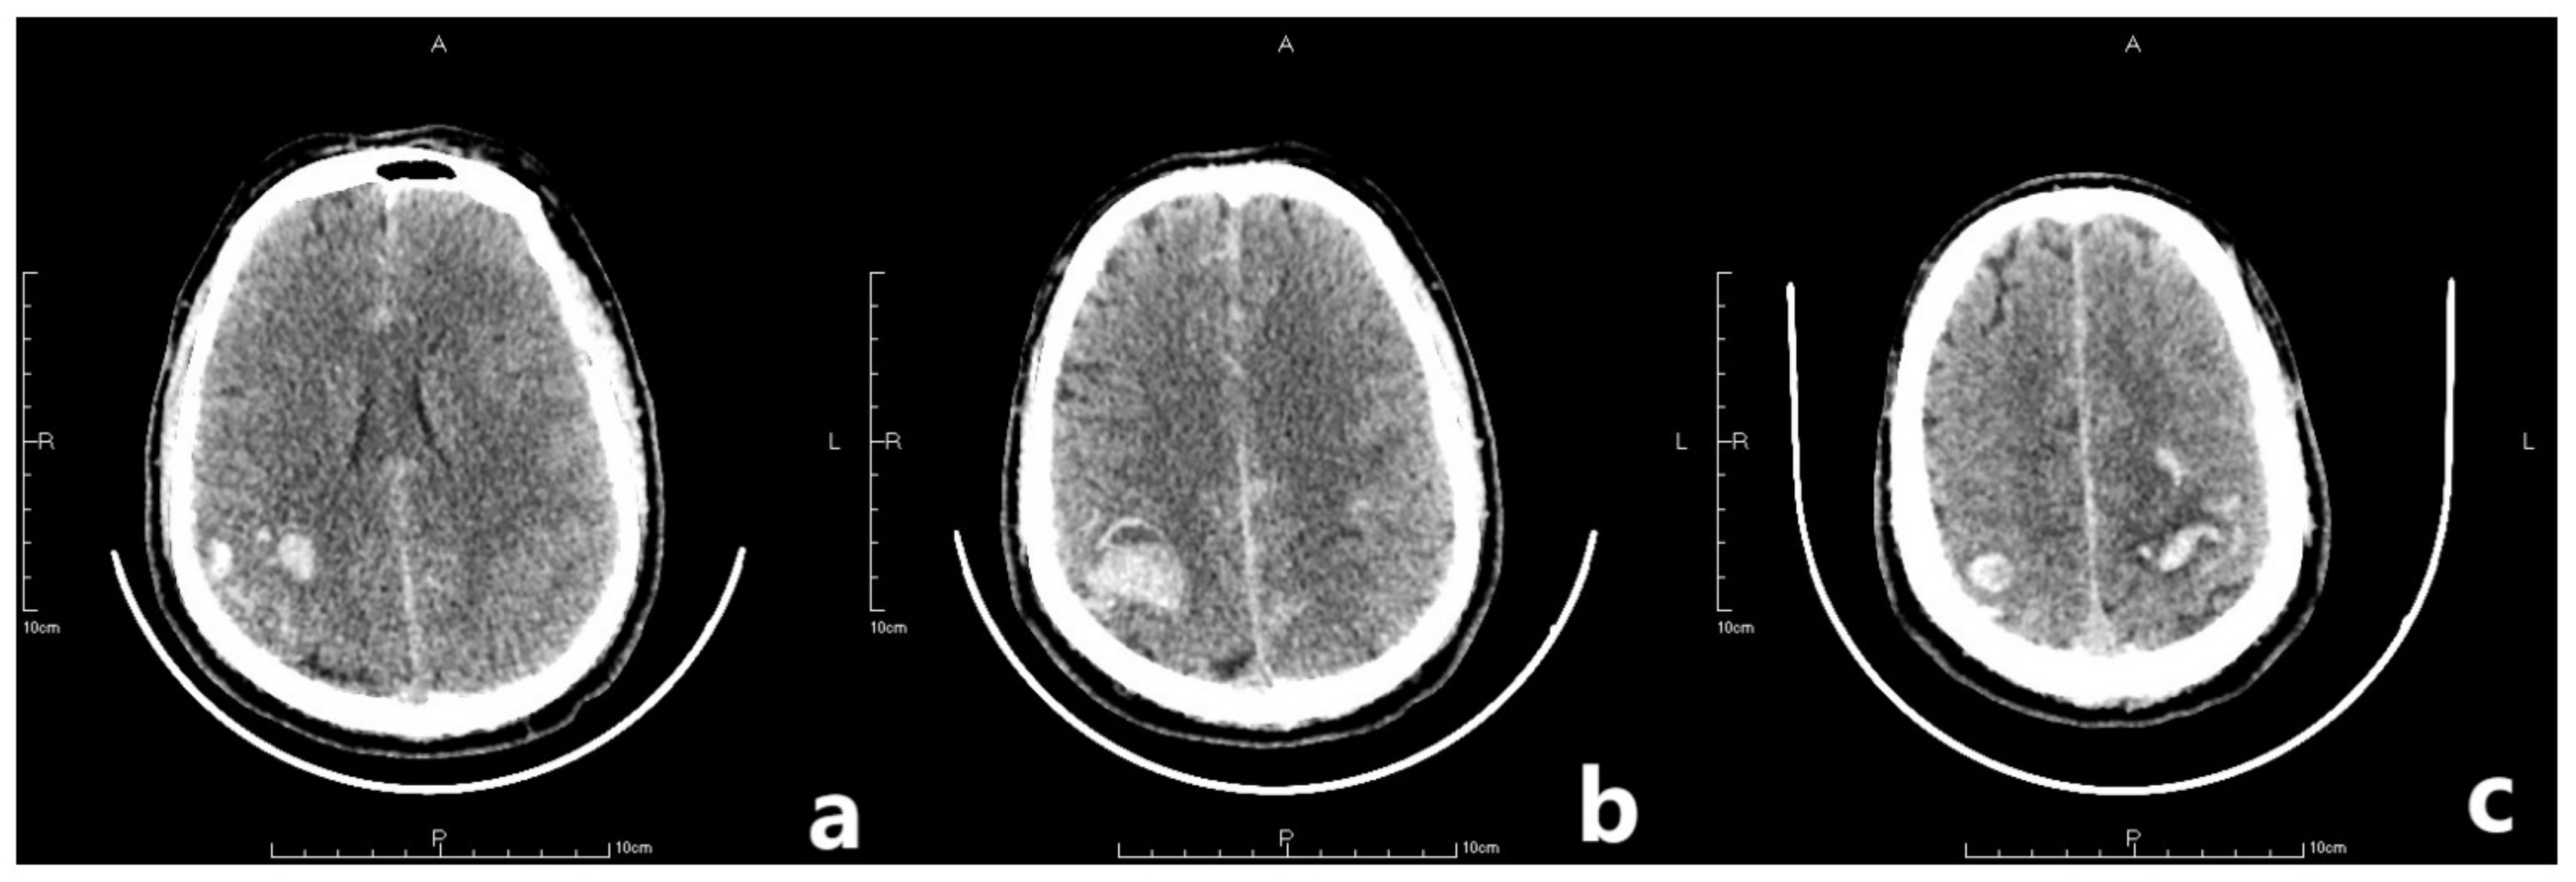

On the second postoperative day, the patient presented with idiopathic unconsciousness, limb twitching, and trismus. An emergency cranial CT scan demonstrated scattered hemorrhages in the bilateral frontoparietal lobes along with subarachnoid hemorrhages and edematous zones around some lesions (Figure 2 and Figure 3). Following an emergency consultation with the Department of Neurology and Neurosurgery, a diagnosis of venous sinus thrombosis combined with multi-focus cerebral hemorrhage was made. As per their orders, the patient underwent an emergency interventional intracranial angiography and thrombectomy.

Figure 2.

The letter R, A, P, L in the figures refers to Right, Anterior, Posterior and Left, respectively. Emergency CT scan showed scattered hemorrhages in bilateral frontoparietal lobes combined with subarachnoid hemorrhage and edema zones around some lesions (a–c).